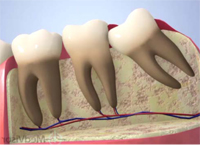

3. ほぼ真横にはえている

|  |

この状態の親知らずは生える事はありません。

見た目も歯茎の中や骨の中にうまっている為解りません。

歯科医院にてレントゲンを撮る事で親知らずがあるかないかが解りますので、一度レントゲンを撮って確認してみましょう。